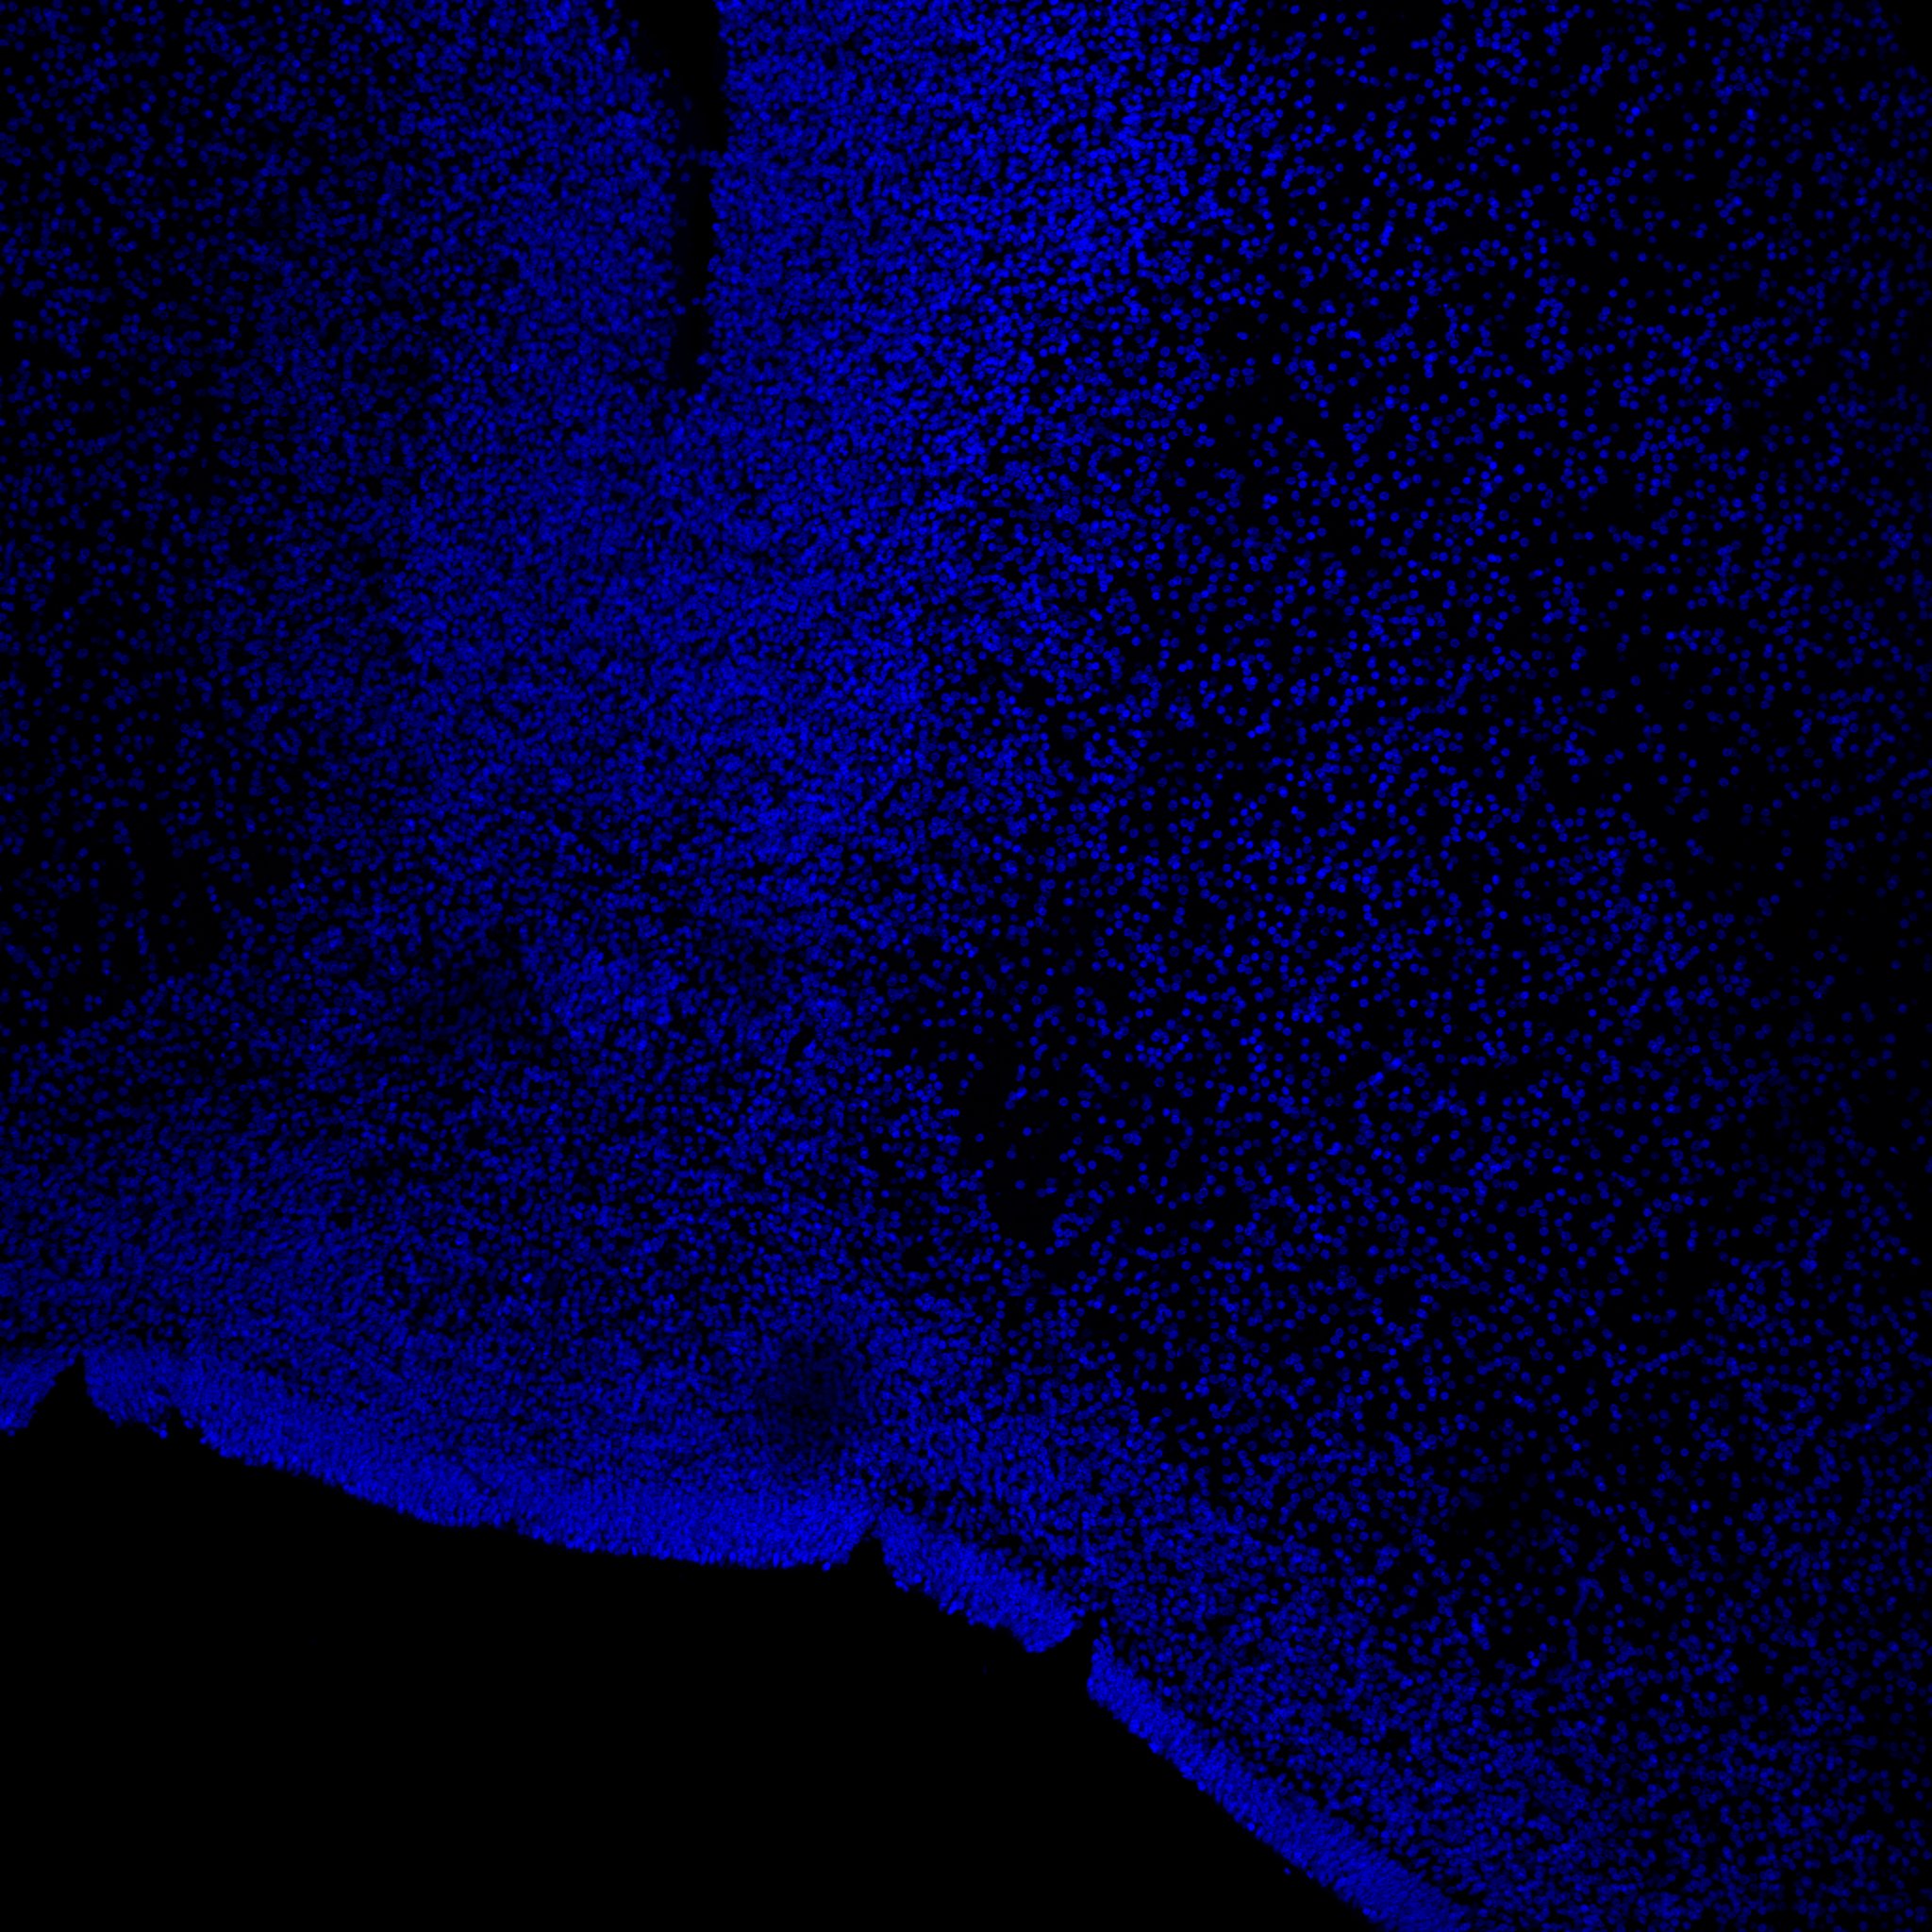

DAPI

6PCW human midbrain